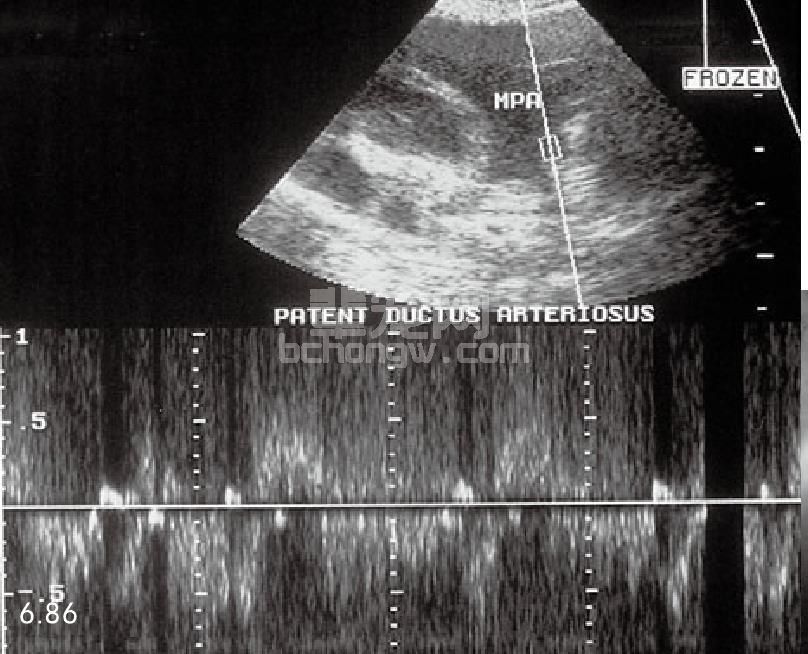

超声波心动描记术 (图6.86)PDA较难成像,但可在肺主动脉与下行的主动脉之间观察。肺主动脉可见肥 大。左心房和左心室肥大呈现充盈过度。左心室最初为运动功能亢进,但长期的病例由于心肌衰竭而其收缩性 (部分缩短)减小。

如果脉冲型多普勒仪样品门放置于肺动脉,尤其是靠近左右侧肺动脉结合处时,可检测到持续性的流动紊乱 及向肺动脉瓣高速率逆流。房室瓣逆流较为常见。

图6.86 患有PDA的7月龄雌性卷毛比雄犬的超声波心动描记,显示肺主动脉持续增大和逐渐减弱的不稳定液流。